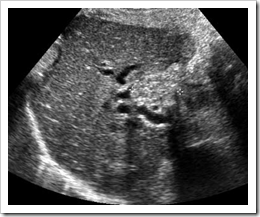

Traditionally, ultrasound images normal lymph nodes are difficult or impossible to demonstrate on ultrasound. However, with good-resolution equipment, and using a suitable acoustic window, such as normal liver tissue normal lymph nodes can be demonstrated in the hepatoduodenal ligament at the porta hepatis (Fig.below),

particularly in younger patients. The search for lymphadenopathy should include the para-aortic and  paracaval regions, the splanchnic vessels and epigastric regions, and the renal hila (Fig. 6.9). Ultrasound has a low sensitivity for demonstrating lymphadenopathy, in the retroperi toneum, as bowel contents frequently obscure the relevant areas. CT or MRI is better able to define the extent of lymphadenopathy, particularly in the pelvis. The presence of lymphadenopathy is highly non-specific, being associated with a wide range of conditions including malignancy, infections and inflammatory disorders. Benign lymphadenopathy is commonly seen in conjunction with hepatitis and other inflammatory disorders such as pancreatitis, cholangitis and colitis.